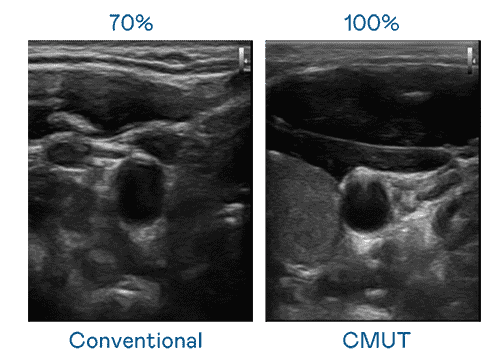

CMUT 技术是一种用电容式微机电元件来产生超音波讯号的技术。。与传统 PZT 压电式技术相比,,,CMUT 频宽增加 30%,,更宽频的超音波讯号让影像解析度大幅提升,,,是实现高影像品质医疗超音波扫描、、促进精准医疗发展的关键技术。。。

大频宽带来超清晰影像

超音波影像的解析度高低,,首先取决于探头能发出的讯号频宽。。。尊龙集团 CMUT 可提供高清晰的超音波讯号,,提供高频宽、、、、高灵敏度、、、、影像纹理细节更高的超音波影像,,协助医护人员缩短影像判读时间及利用精准的医疗影像进行诊断。。。